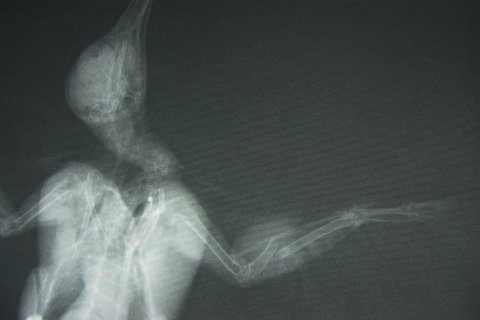

厚岸から建物に衝突したヒヨドリが運ばれてきました。レントゲン検査の結果、左の前腕を骨折していました。鳥類では太い方の尺骨は3つに割れ、細い橈骨も根本で脱臼していました。

輸液などを施した後、全身麻酔(ガス麻酔)をかけて骨をつなぐ手術を行いました。骨折部位に合ったピンを注射針を用いて自作し、割れた骨をつなぎ止めました。脱臼した橈骨も元の位置に整復しました。